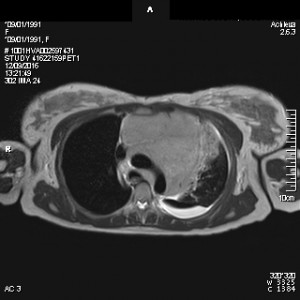

Se observa una masa en hemitórax izquierdo que desvia la tráquea hacia el lado derecho, y un derrame pleural izquierdo en la base que ocupa el seno costofrénico izquierdo. Se realizó una RM de tórax para estudiar con más detalle la masa y evitar más radiación (TC), dada la edad de la paciente, y la masa se localizó en el mediastino.

DIAGNÓSTICO FINAL: Linfoma mediastínico.

Los linfomas son neoplasias malignas del sistema inmune, que se producen a través de proliferaciones clonales de poblaciones de linfocitos en distintos estadios evolutivos. Pueden ser células T o células B. Puede aparecer en el mediastino, en cuyo caso se visualizará como una masa en la radiografía simple de tórax, o en una RM.